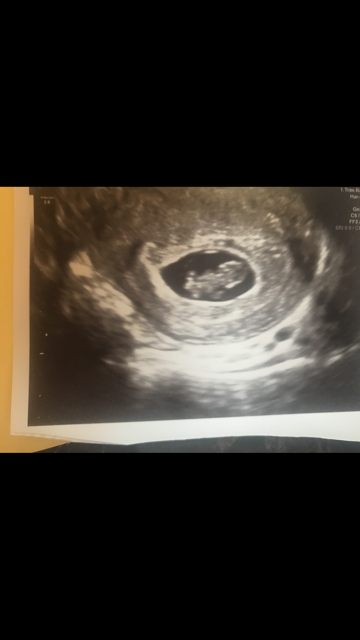

Gender guesses?? Please! Sonogram at 8 weeks Done transvaginal. Thanks! ;)